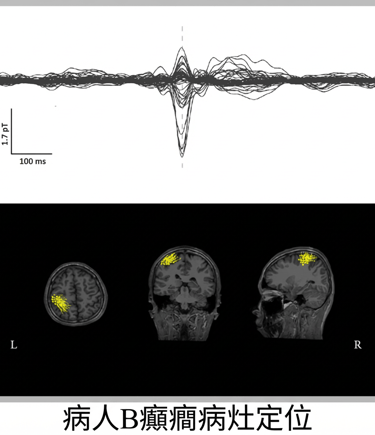

癲癇致癇灶定位

癫痫病例